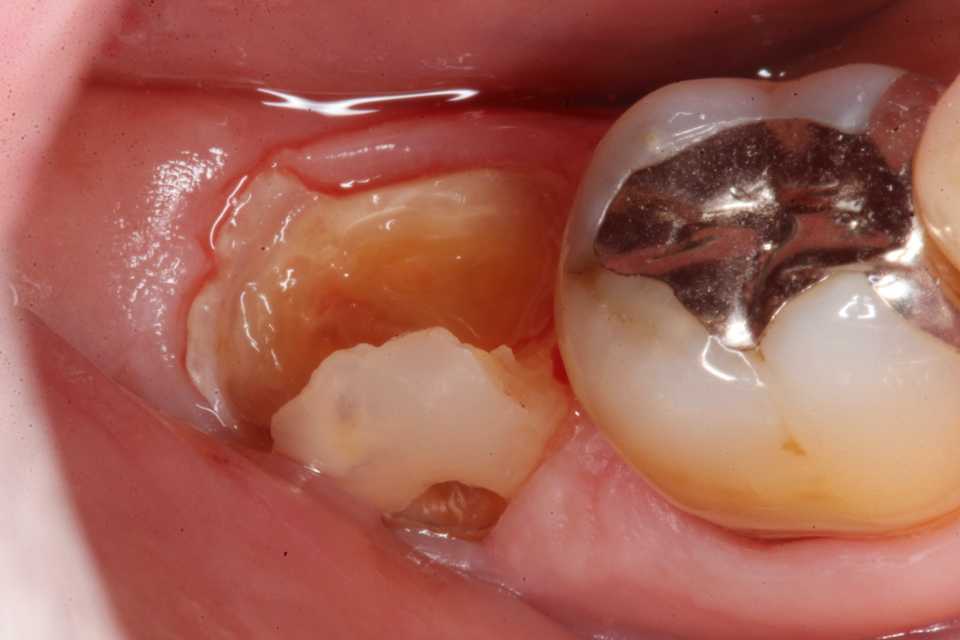

ストリップスを使わない隣接面CR(ダイレ… 2025.11.26

ストリップスを使わない隣接面CR(ダイレ… 2025.11.07